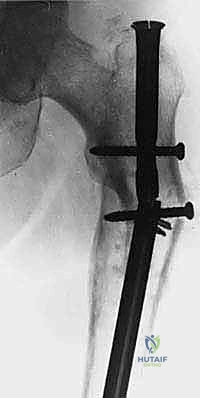

1. التثبيت الوقائي الداخلي (Prophylactic Internal Fixation)

إذا أظهرت الأشعة أن العظم ضعيف جداً وعلى وشك الانكسار، يقوم الدكتور هطيف بوضع أسياخ نخاعية معدنية (Intramedullary Nails) أو شرائح ومسامير متطورة داخل العظم لتدعيمه ومنع الكسر قبل حدوثه. هذه الجراحة الاستباقية توفر على المريض آلاماً مبرحة ومضاعفات خطيرة.

| جسم عظم الفخذ أو الساق | كسر مرضي كامل أثناء التحميل. | التثبيت بمسمار نخاعي تشابكي (Intramedullary Nailing). |

- الحالة الأولى: سيدة تبلغ من العمر 55 عاماً، متعافية من سرطان الثدي، عانت من ألم مبرح في الفخذ الأيمن وعجز كامل عن المشي بسبب كسر مرضي وشيك. بعد إجراء الفحوصات، قام الدكتور هطيف بإجراء جراحة تثبيت وقائي باستخدام مسمار نخاعي. في غضون 48 ساعة، استطاعت السيدة المشي بدون ألم، وعادت لممارسة حياتها وسط عائلتها.